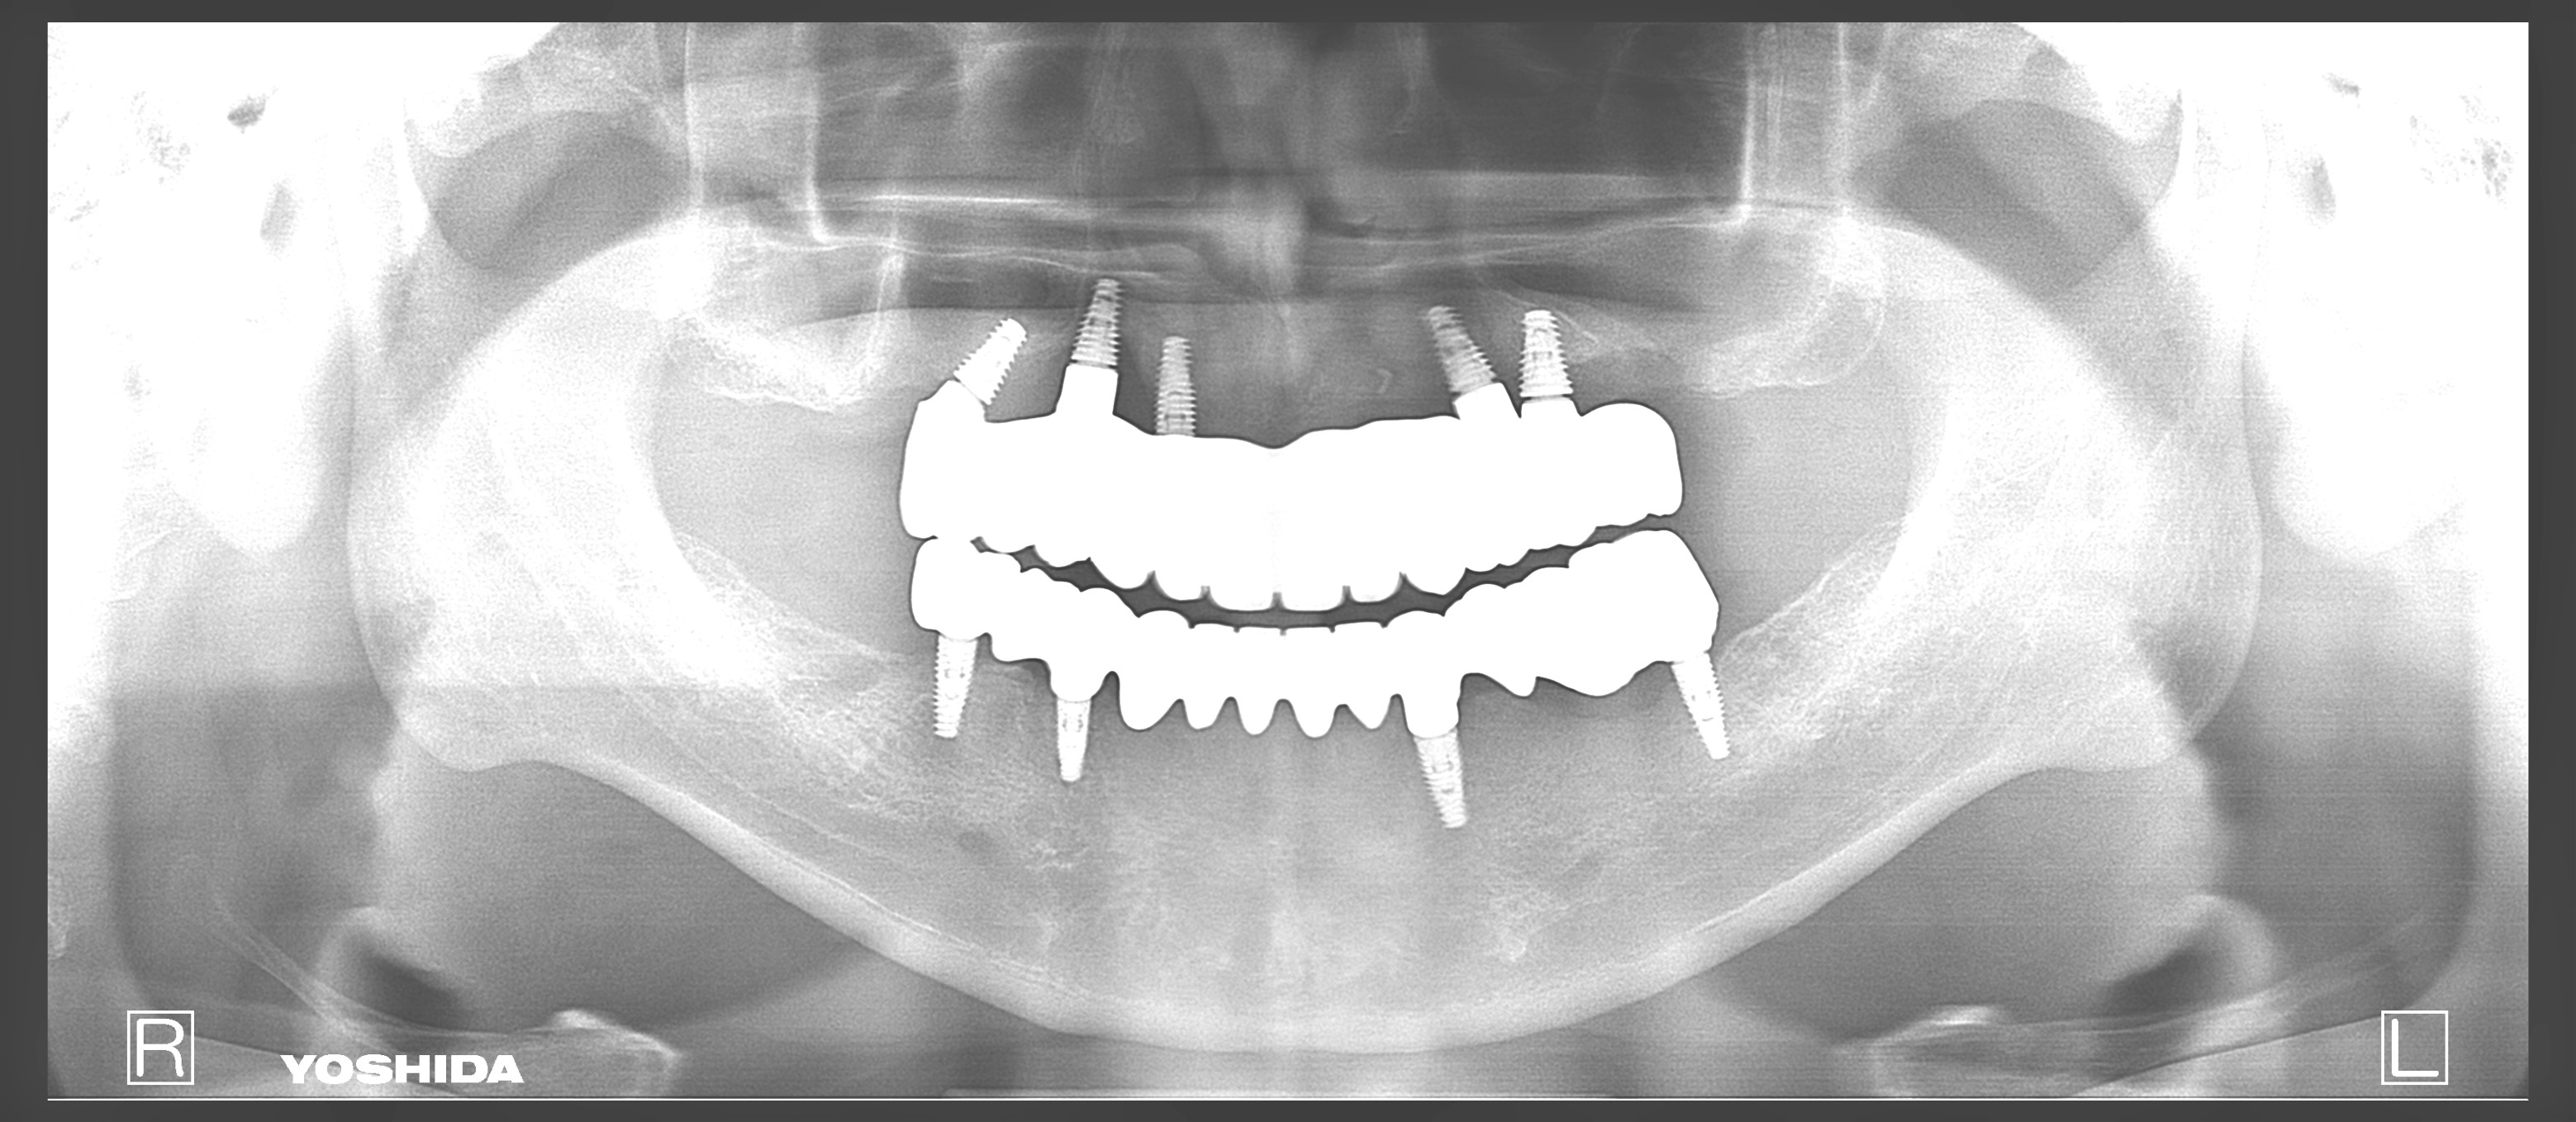

父のレントゲン写真と口腔内を見て、インプラントを入れる位置を一緒に決めて行きました。

左側の入れ歯を入れていたと言っている場所には通常の方法でインプラント治療を、左上の奥歯2本は歯周病でグラグラだったため抜歯と同時にインプラントと治療を行いました。

左側のレントゲンがが最初の状態です。右側がインプラントを入れ、被せ物まで入れた状態のレントゲンです。